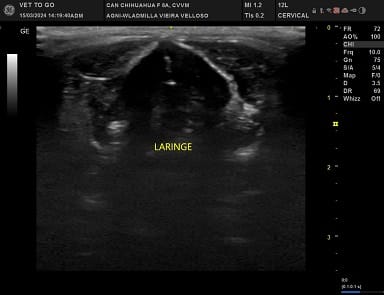

Imagens de Ultrassom Cervical Veterinário

O Ultrassom Cervical é um exame que pode ser realizado em cães e gatos e é de grande auxílio para investigar alterações na região do pescoço ventral. Através dele é possível avaliar a vascularização da região, linfonodos regionais, glândulas salivares, esôfago cervical, língua, musculatura, traquéia, laringe, tireóide e paratireóide.